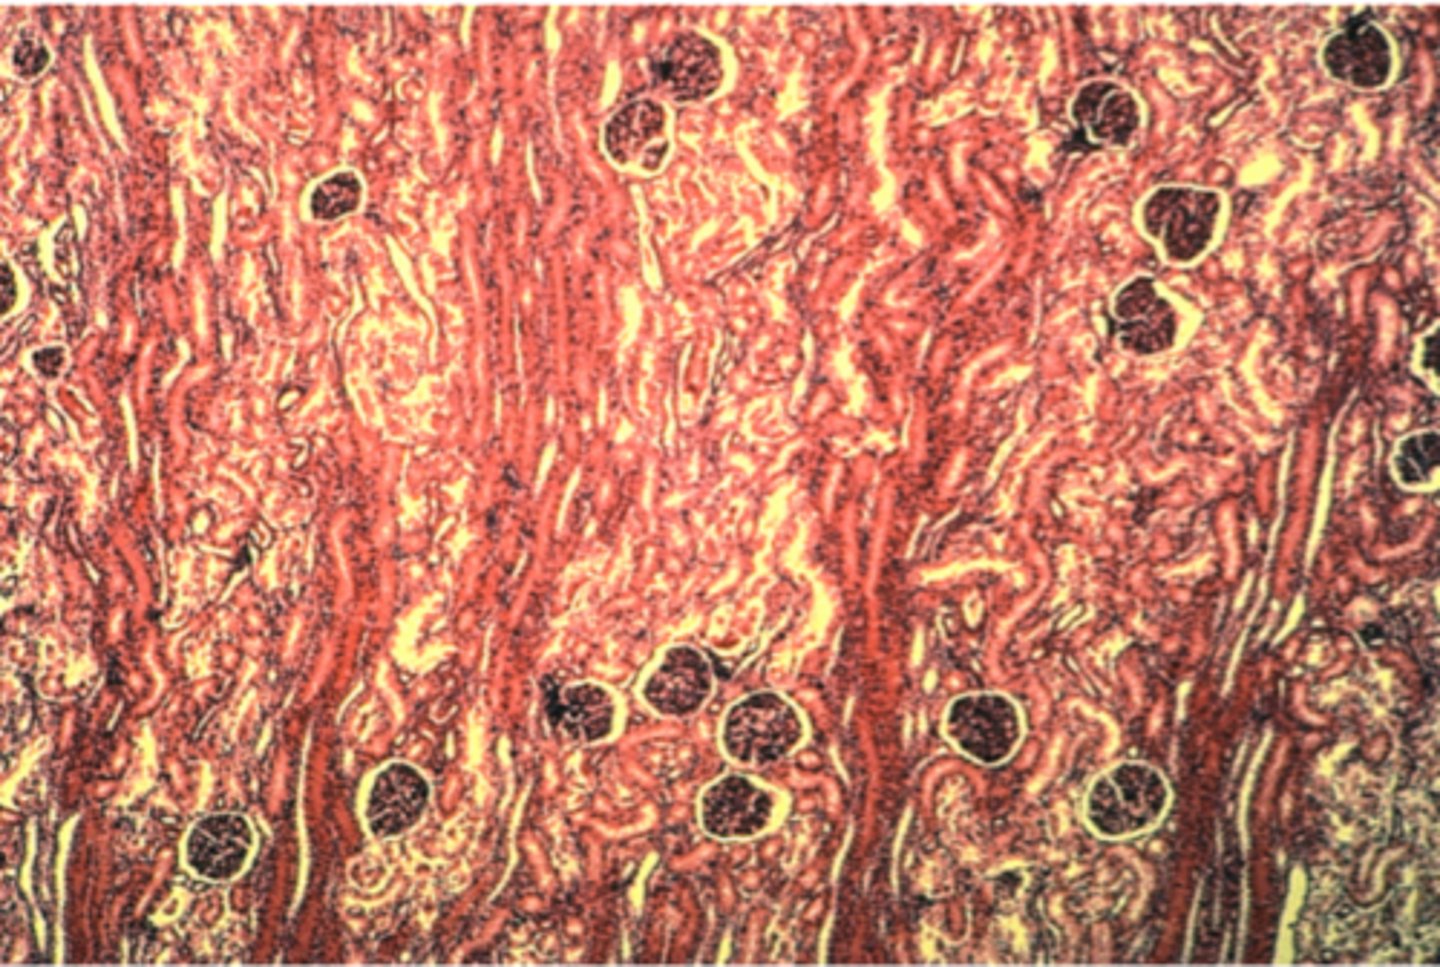

Glomerulus in kidney

What is this?